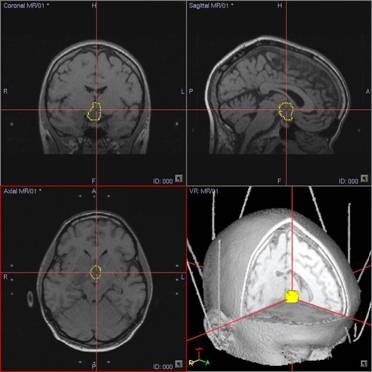

2. Планирование траектории доступа для стереотаксической биопсии и для установки гибкого интрастата производилось на стереотаксической планирующей системе Stryker Leibinger по МРт и КТ реконструкциям, в том числе и в режиме 3D. Траектория из премоторного доступа в правом полушарии, проходящая через отверстие Монро в геометрический центр опухоли.

3. Сборка стереотаксической дуги в операционной.

4. Биопсия спиралью. Гистологический вариант опухоли – фибриллярно – протоплазматическая астроцитома.

5. Установка интрастата.

6. Планирование и реализация облучения. Планирующая система Abacus. Аппарат для брахитерапии Gamma Med + с источником Ir192